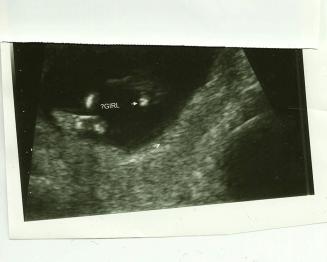

Hi there. I'm new to this board AND to this NUB theory stuff. Last week at my first trimester screening the tech said 80% it was a girl!! I go to a high risk perinatologist who does this a lot, so I was THRILLED...but now I'm nervous and doubting! The first pic is a potty shot, which I understnad isn't super reliable at 12 weeks 4 days...but that was what she showed me. The second is what I "believe" is a nub...but I'm not really sure. I'd love any input you all have to give!! THANK YOU!!!!!!

the nub looks flat, that means girl, but you cant tell by a potty shot that early because boy and girl are made the same at that stage but you can tell with the nub theory and its 80% accurate a 12 weeks. I would still say a girl because of the nub.